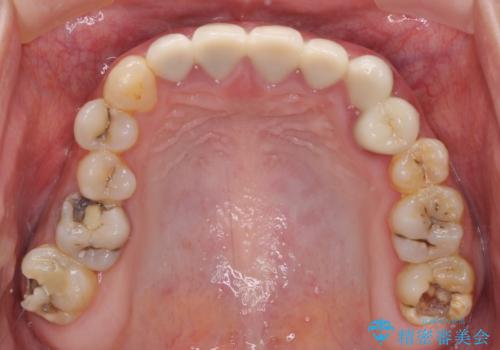

むし歯だらけの奥歯 セラミッククラウンによるむし歯治療

- 奥歯のむし歯を気にして来院された患者様です。

痛みのある歯が多く、根管治療が必要と診断されました。

左下の歯は、クラウンを装着するために必要な高さが足りないため、歯冠長を延長するための外科処置を行うこととしました。

根管治療や歯周外科処置後にフルジルコニアクラウンにて補綴治療することとしました。

自身の口腔内への意識が高くなく、汚れが非常に多い方でした。